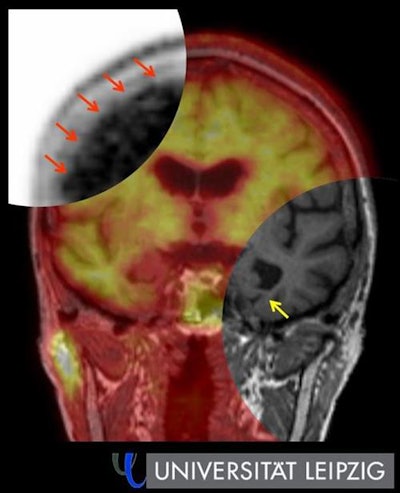

PET scans, either on their own or in combination with MRI, provide an anatomical overview of dementia patients' brains. They also offer precise molecular information about the nature and extent of the disease -- even at an early stage. This is valuable both in clinical research and patient care, and should be a normal part of the imaging professional's repertoire, according to Dr. Henryk Barthel, professor of nuclear medicine clinic at Leipzig University Hospital.

Traditional FDG-PET reveals glucose uptake and thus the tissue's energy metabolism, while amyloid PET, which has been the subject of extensive research for some time now, is more helpful in dementia diagnosis because it reveals the amyloid protein deposited in the brains of Alzheimer's patients. "This allows us to see the disease years before brain volume starts to decrease and to better distinguish Alzheimer's from other forms of dementia."

Barthel said the future lies in a hybrid of PET and MRI. "Combined imaging using both techniques gives us a detailed picture of the anatomical and functional aspects of dementia. It's particularly suitable for routine clinical use because patients only have to visit once and we get all the key data we need from the examination."